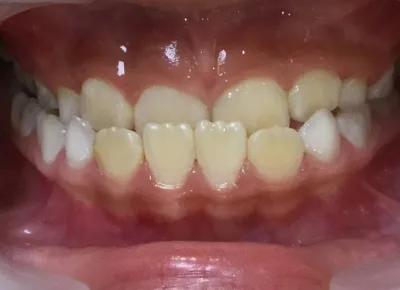

Before

After

治療期間

費用総額